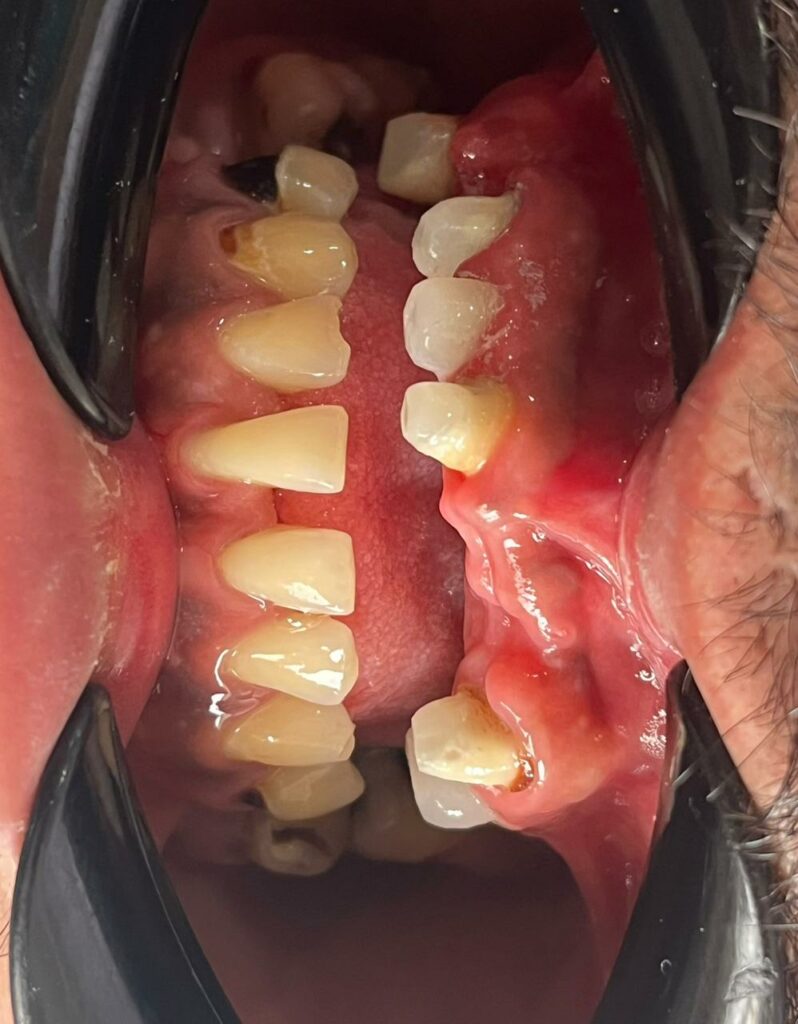

Le remodelage du sourire est un ensemble de techniques esthétiques et fonctionnelles permettant de transformer ou d’harmoniser le sourire.

Il peut associer plusieurs soins tels que :

Le remodelage du sourire s’adresse à toutes les personnes souhaitant :